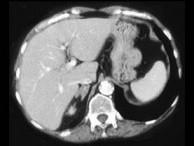

问题 女,42岁,夜尿增多伴高血压,实验室检查:血和尿醛固酮水平增加,请结合图像,选择最佳答案()

选项 A.双侧肾上腺增生 B.双侧肾上腺腺瘤 C.双侧肾上腺未见异常 D.双侧肾上腺转移瘤 E.双侧肾上腺淋巴瘤

答案 A